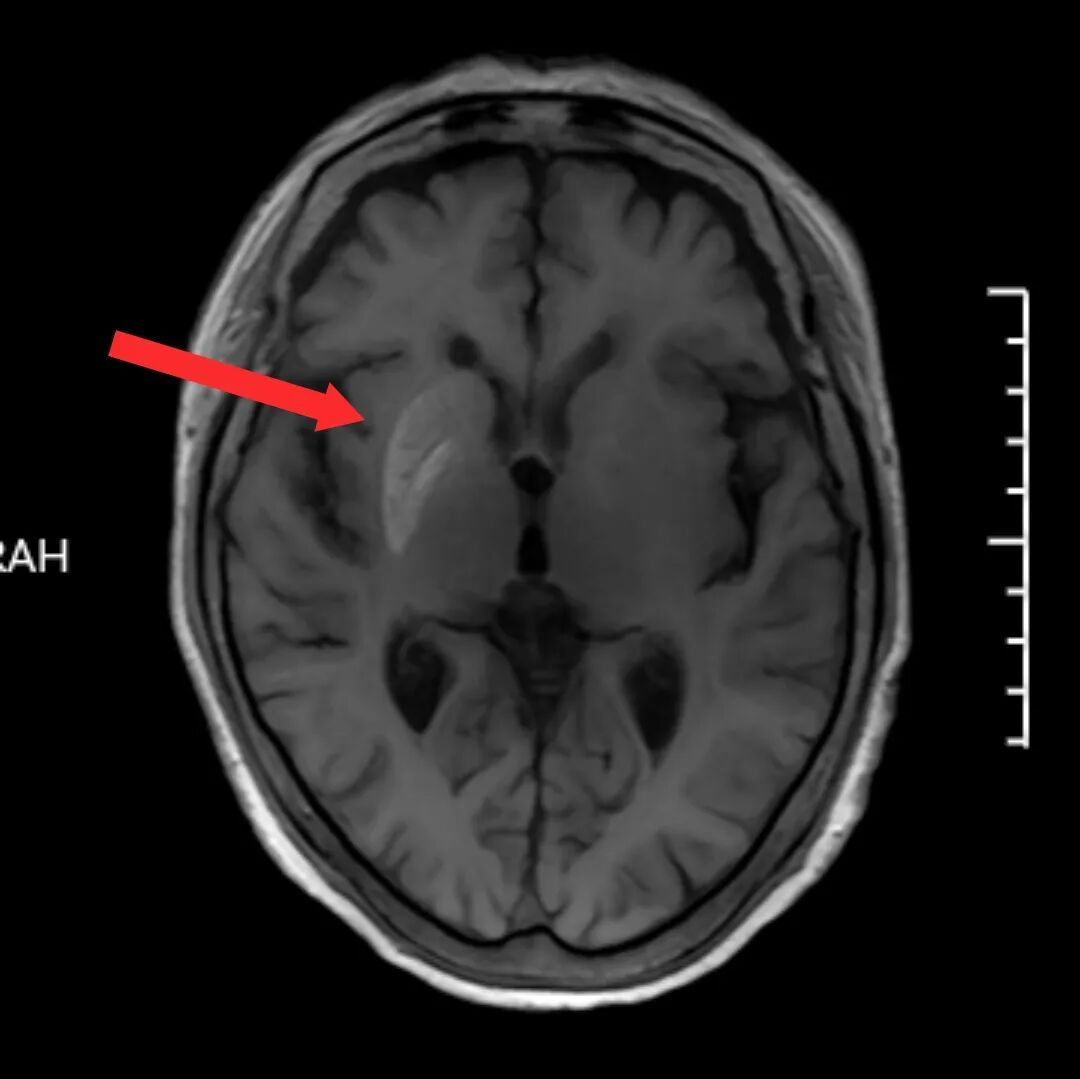

头颅磁共振(MRI)检查显示一个关键线索,在影像上可以看到,孙奶奶右侧大脑豆状核区域显示出异常高信号,而在其他序列中该区域并无明显异常。这一特异性影像表现,引起了放射科主任陈子虎的高度重视。

他迅速组织团队集体阅片讨论。由于患者有长期糖尿病史、血糖控制不佳,虽未出现酮症酸中毒等急性并发症,但结合其症状以及MRI上特征性表现,应重点考虑与代谢相关的罕见疾病。

“该病多见于血糖控制不良的老年糖尿病患者,尤其是女性。其典型影像学标志也与患者影像表现高度吻合。”通过老年医学科与放射科的多学科会诊,胡安定医疗团队逐步排除了脑卒中、肿瘤、颅内感染、免疫性脑炎等常见病因,最终锁定病因——非酮症高血糖性偏侧舞蹈症。该病的根本机制在于长期高血糖对大脑基底节区神经细胞代谢的影响。